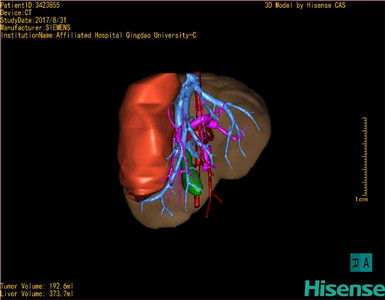

将0.625mm双源薄层CT资料的静脉期和动脉期Dicom格式文件导入海信CAS系统。

通过调节窗宽窗位调整CT序号,对肝实质,胆囊,下腔静脉,肿瘤,肝动脉、门静脉及肝静脉等进行三维重建;系统自动计算肝脏体积。

模拟手术操作,自动计算切除肿瘤体积。肝脏体积为373.7ml,肿瘤体积是192.6ml,是肝脏体积的0.5倍,通过比对2-3岁正常肝脏体积为475.97±99.7ml,通过术前模拟手术,精准判断切除后剩余肝脏体积能耐受,避免肝衰竭发生。

术前三维重建:

重建图片